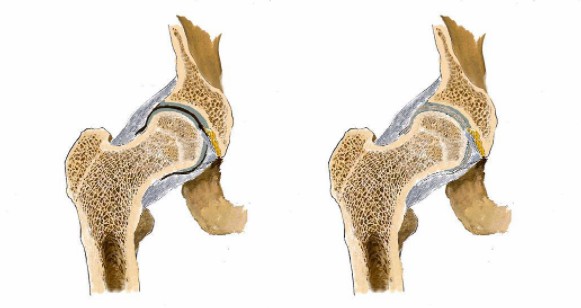

看男孩不說話,醫(yī)生繼續(xù)說道:“你的HLA-B27顯示陰性,如果是陽性就可以確診是強直性脊柱炎,現(xiàn)在只能排查……如果確診是強直性脊柱炎,就要就要及早治療,因為這個病是不可逆的,我們只能延緩它病程進度……”

“你這沒事!腿痛就是有點水腫炎癥導(dǎo)致的,注意休息鍛煉適度就會好的。”